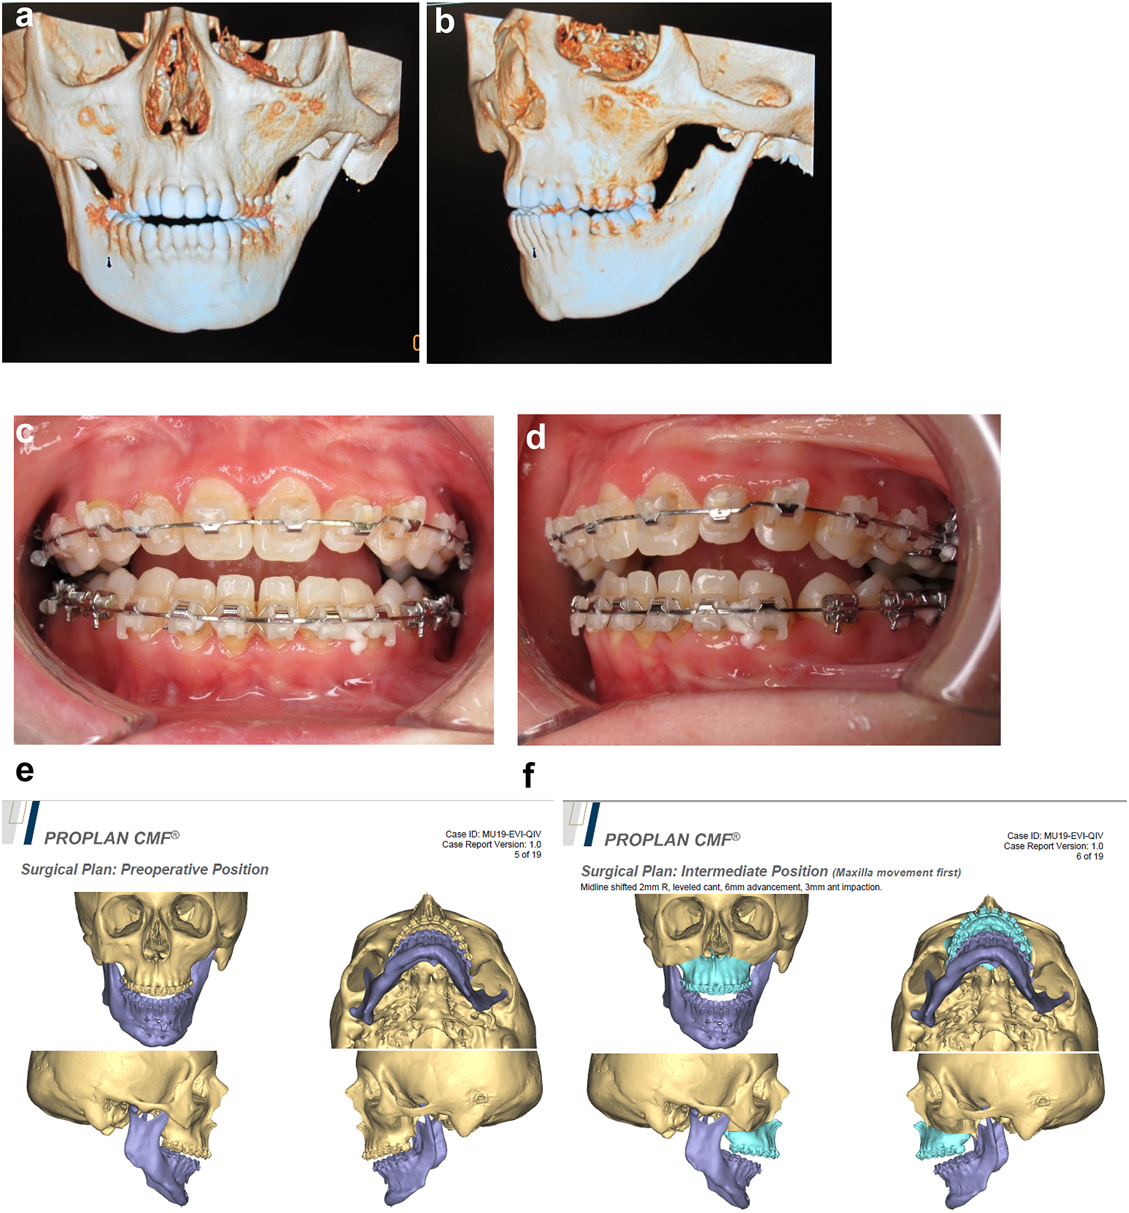

Later she required vertical lenghtening of the left mandibular ramus by distraction and, as described on Page 11, it is important to perform the osteotomy for that distraction within the original mandibular bone and not in the consolidated rib graft, in the area ringed in yellow on the post-rib graft CT scan below (Figure 21).

Figure 21:

Planning of end stage reconstruction (same patient as Figure 20) by orthodontics and bimaxillary rotational osteotomies. (a and b) Same patient as Figure 20 at 15 yrs of age. (c–f) 3D pre-op and plans for the maxillary osteotomy.

Planning of end stage reconstruction (same patient as Figure 20) by orthodontics and bimaxillary rotational osteotomies. (g) Plans for the bimax osteotomies. (h and i) Plans for printing of 3D plates for fixation of maxilla and mandible osteotomies, (j and k) Clinical outcome.